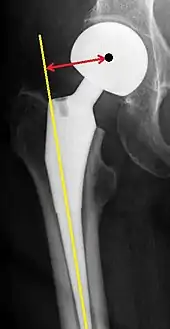

The direction of the acetabular cup influences the range of motion of the leg, and also affects the risk of dislocation.[9] For this purpose, the acetabular inclination and the acetabular anteversion are measurements of cup angulation in the coronal plane and the sagittal plane, respectively.

Center of rotation: The horizontal center of rotation is calculated as the distance between the acetabular teardrop and the center of the head (or caput) of the prosthesis and/or the native femoral head on the contralateral side.[80] The vertical center of rotation instead uses the transischial line for reference.[80] The parameter should be equal on both sides.[80]